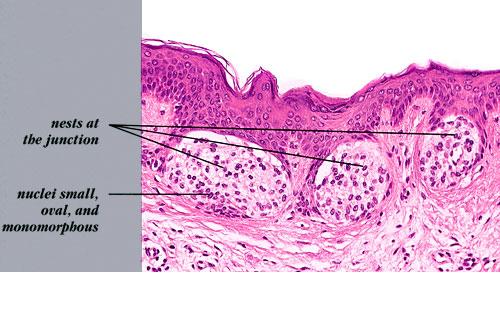

Junctional melanocytic naevus= الوحمة ميلانية الخلايا الوصلية